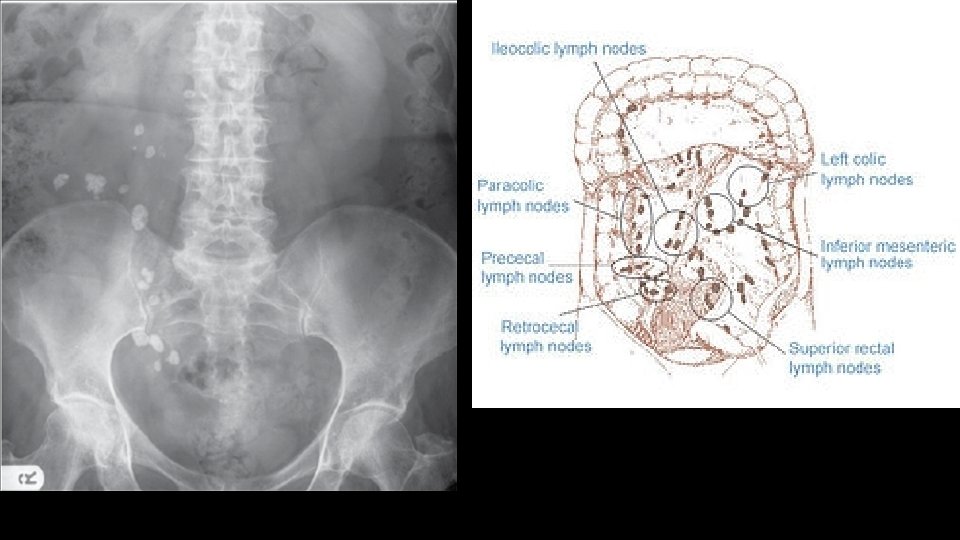

Urolithiasis Calculi along urinary tract • Anywhere • Kidney • Ureter • Bladder

C for calcifications • Calculi – here, there and everywhere • Organ calcifications

ABC of abdominal radiographs • A for Air • B for Bowel • C for Calcification